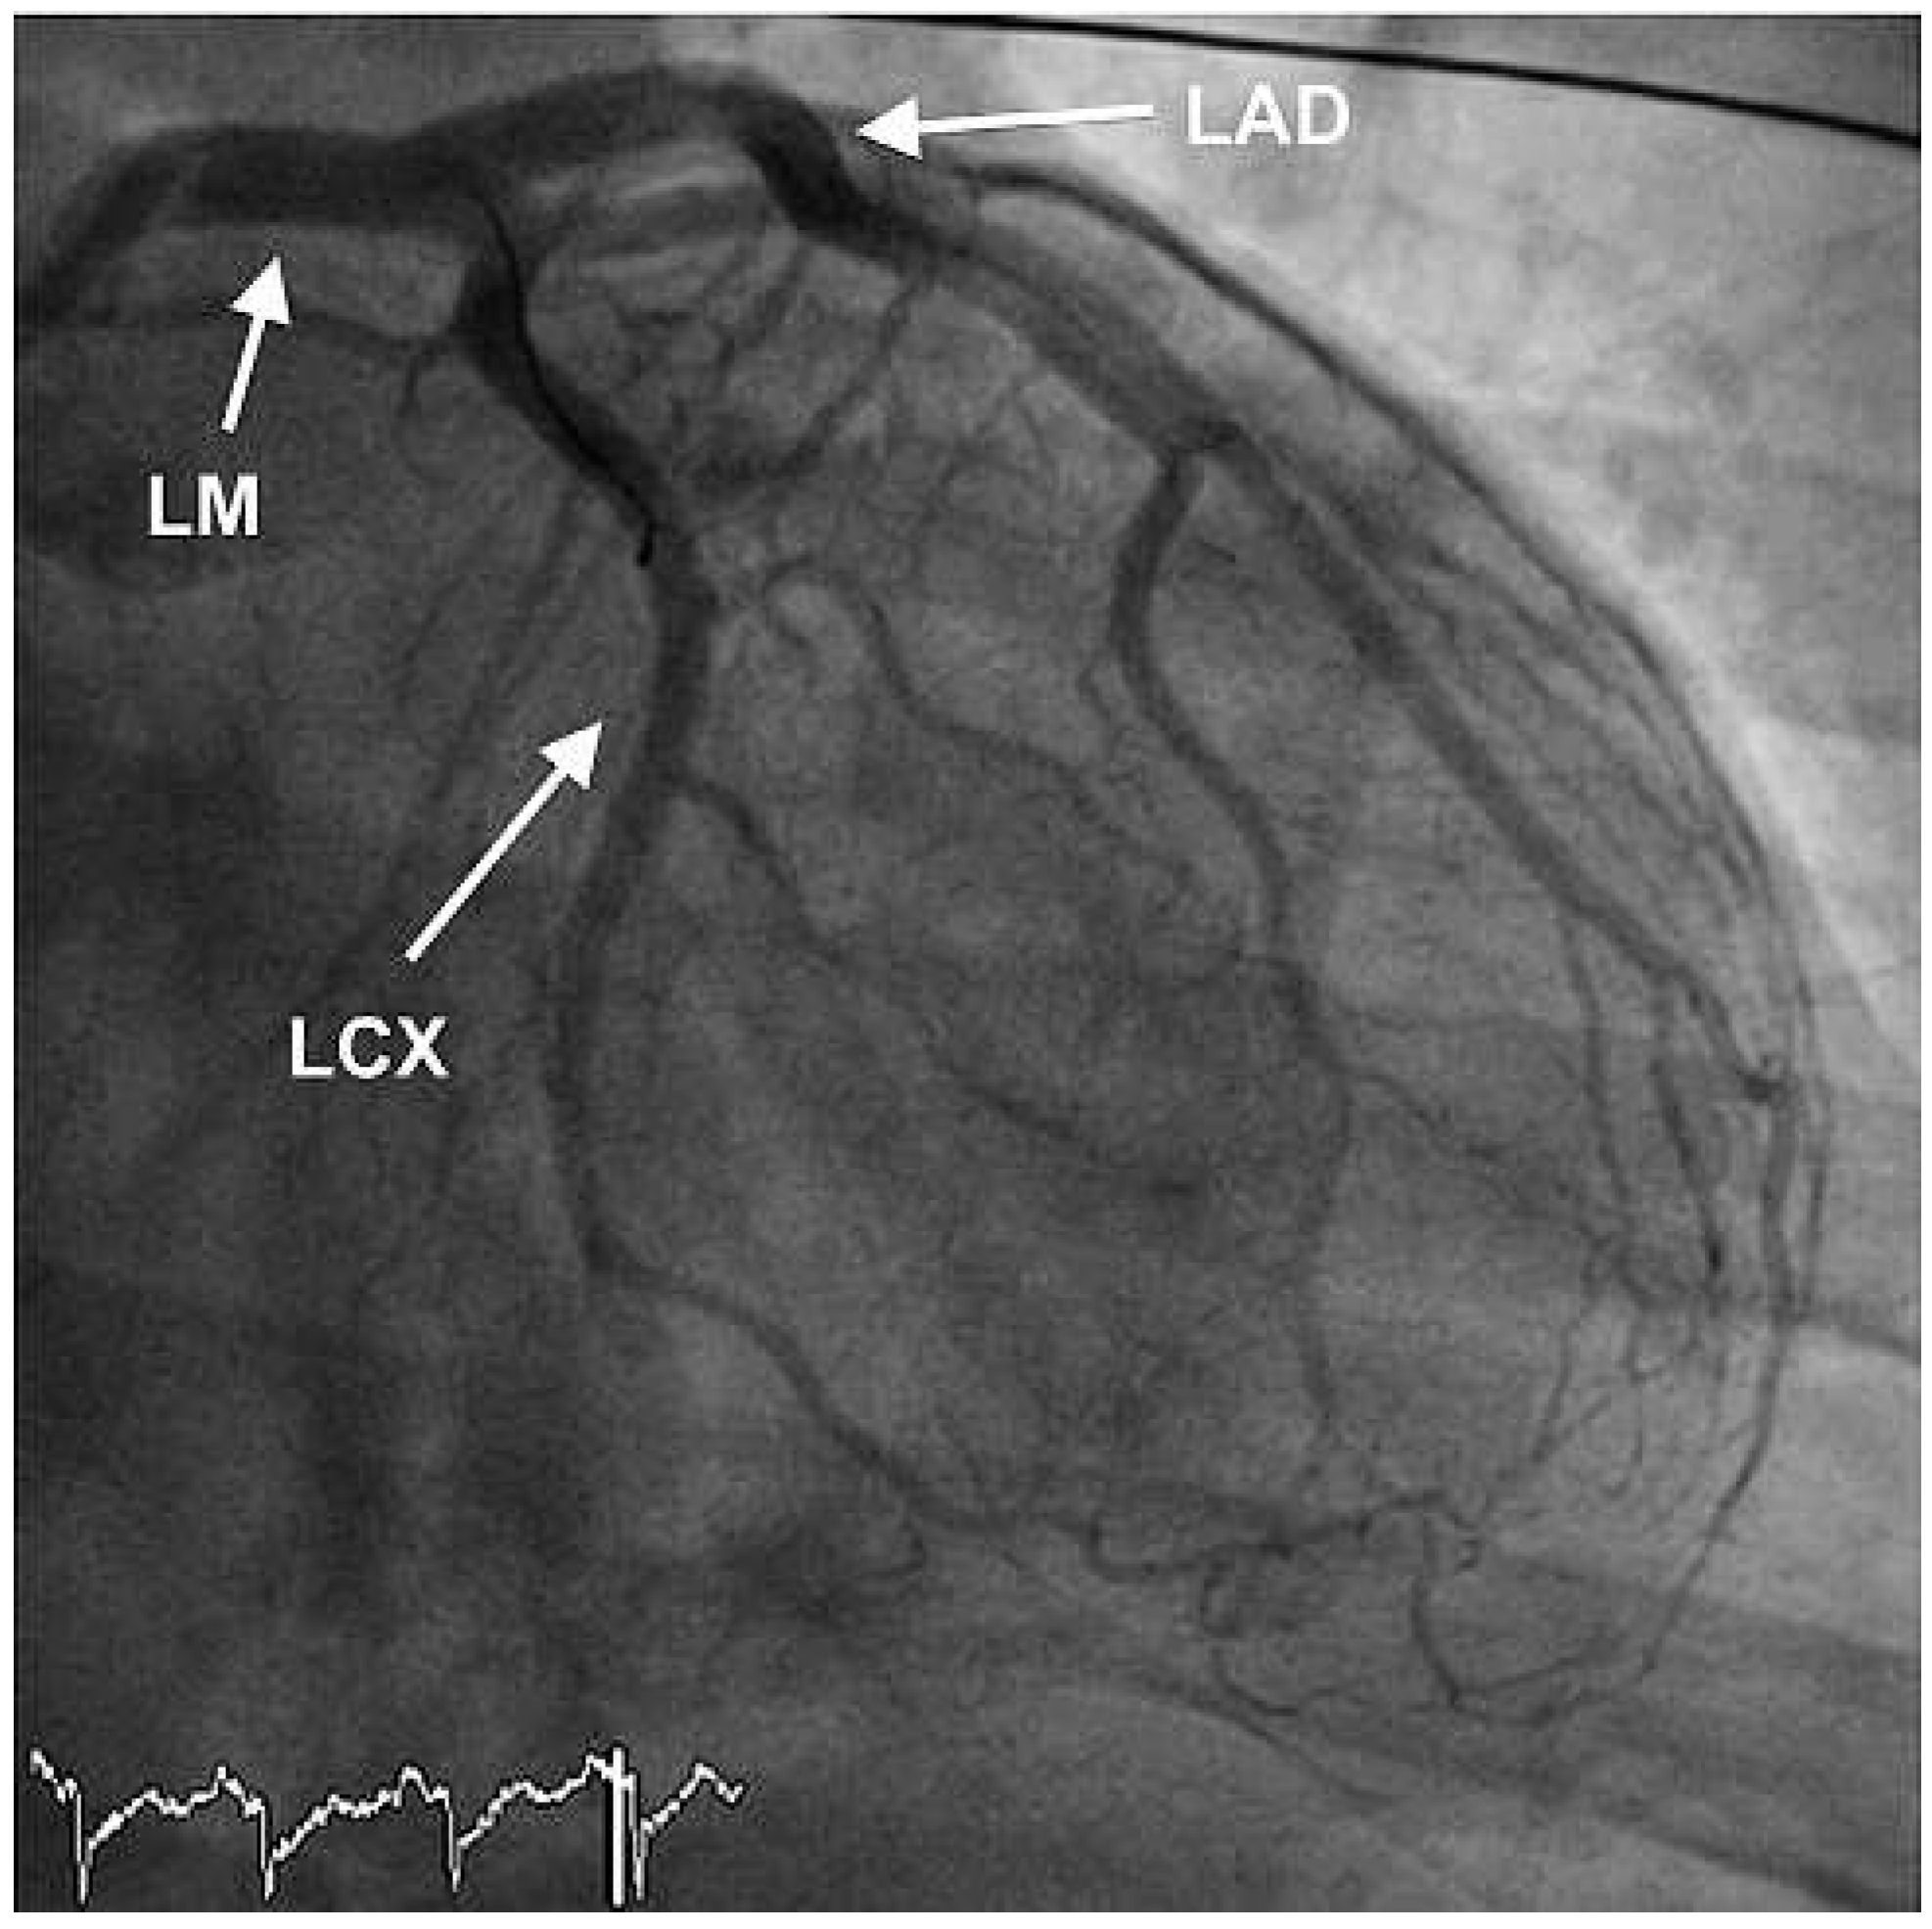

The ECG at admission showed normal sinus rhythm and ST-segment changes in the infero-lateral and the antero-septal leads (Figure 1). The initial troponin and CK-values were normal. Clinically the patient was in cardiogenic shock. Urgent invasive assessment revealed a severely depressed LV-function (EF 30%) with apical, anteroseptal and posterolateral akinesia. There was a total thrombotic occlusion of the mid LAD and the distal circumflex artery (Figure 2).

Figure 2. RAO view showing occlusion of the mid-LAD and of the left circumflex artery. LM = left main coronary artery; LAD = left anterior descending artery; LCX = left circumflex artery.